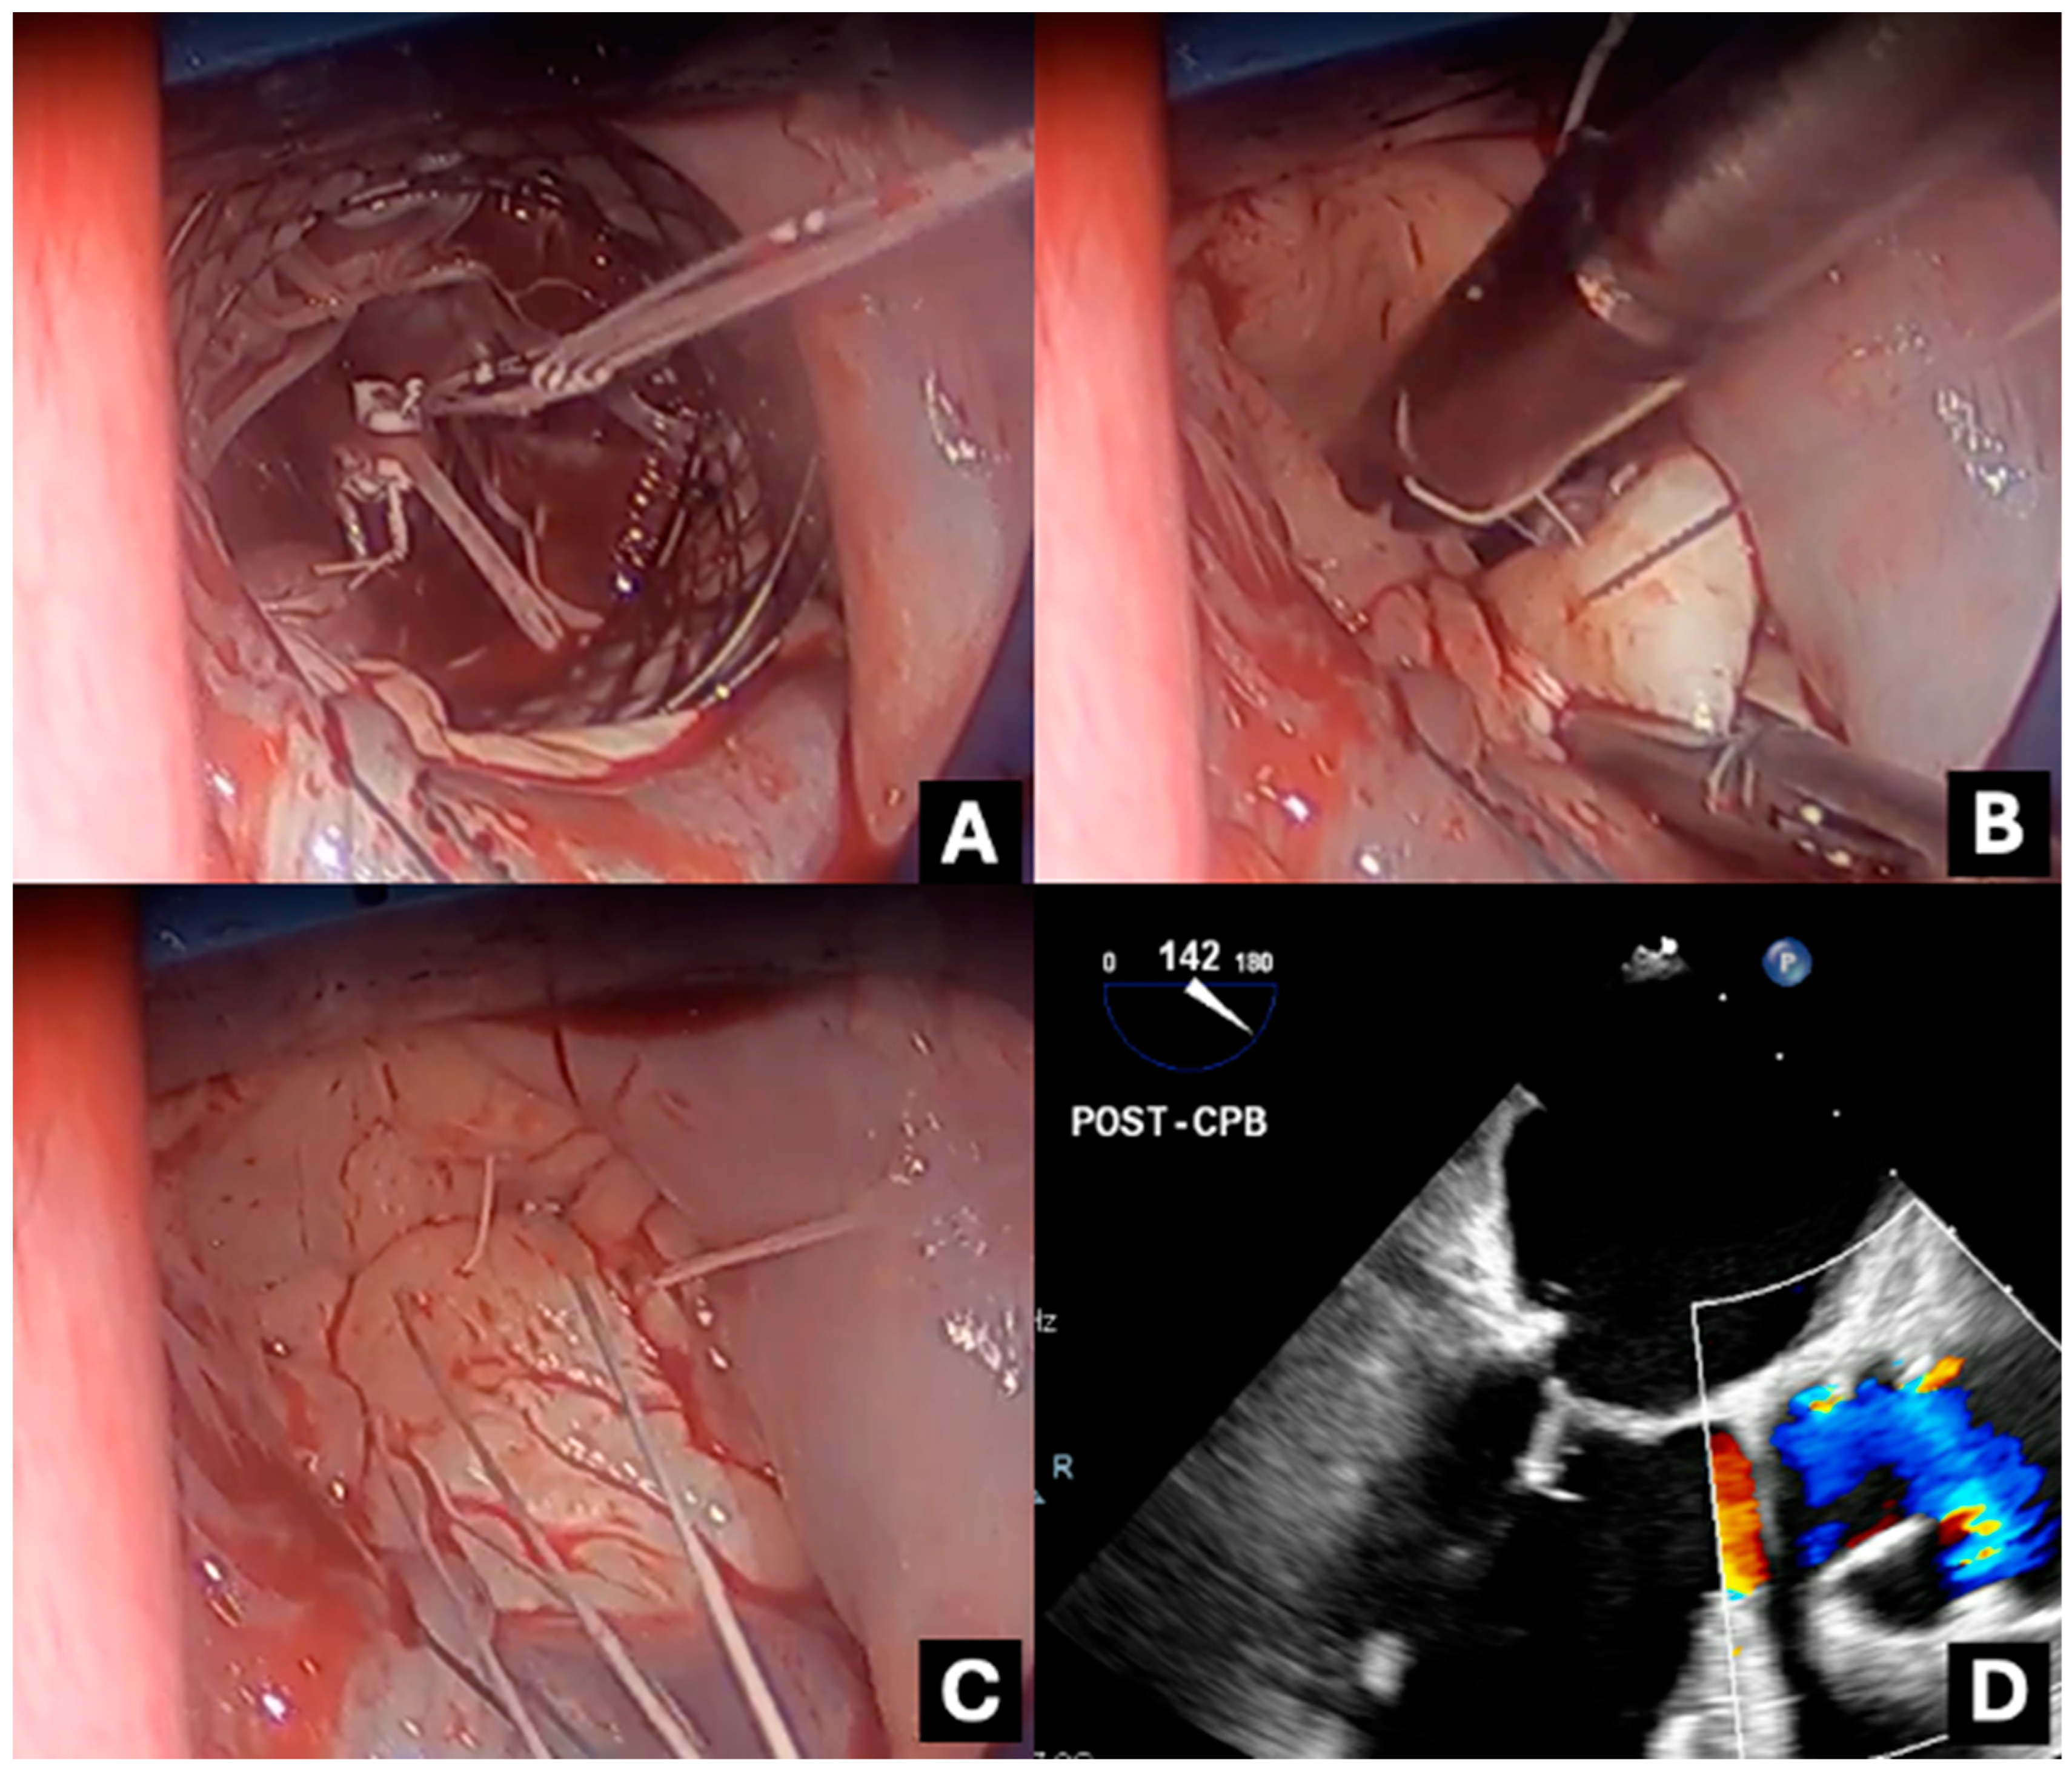

Each Chord-X Pre-Measured Loops set includes a central pledget with two free needles exiting from one side and three pre-configured chordal loops (with attached needles) emerging from the opposite side (Figure 1). The threads are composed of expanded polytetrafluoroethylene (ePTFE). The two free needles anchor to the fibrous portion of the papillary muscle and tie onto a second free pledget (Figure 2A). The chordal loops are subsequently sutured via their associated needles to the diseased mitral valve leaflets and tied (Figure 2B,C). The number of knots and tension in the knot does not change the neochordae size. Although each set has three loops, attaching all loops to the valve is not mandatory. Unused loops can be discarded without compromising the system’s integrity or strength. Post-cardiopulmonary bypass (CPB) trans-oesophageal echocardiography (TOE) is used to confirm the adequacy of repair (Figure 2D).

Figure 2. Intra-operative photography and TOE imaging demonstrating: (A) pledget fixation of the Chord-X system onto the posteromedial papillary muscle, (B) suturing of loops onto the P2 leaflet edge, (C) all loops attached to the P2 leaflet edge, and (D) mid-oesophageal long axis view post-repair exhibiting adequate coaptation of mitral valve; the neochord is faintly seen attaching to posterior aspect of the valve.